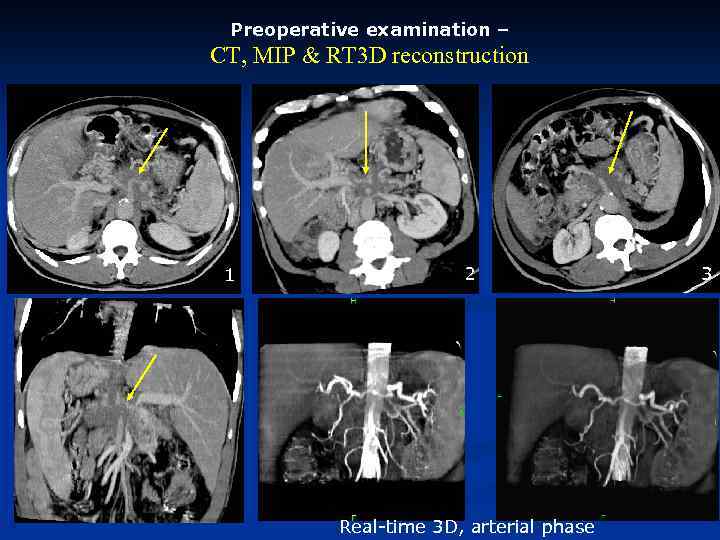

Preoperative examination – CT, MIP & RT 3 D reconstruction 1 2 Real-time 3 D, arterial phase 3

Preoperative examination – CT, MIP & RT 3 D reconstruction 1 2 Real-time 3 D, arterial phase 3